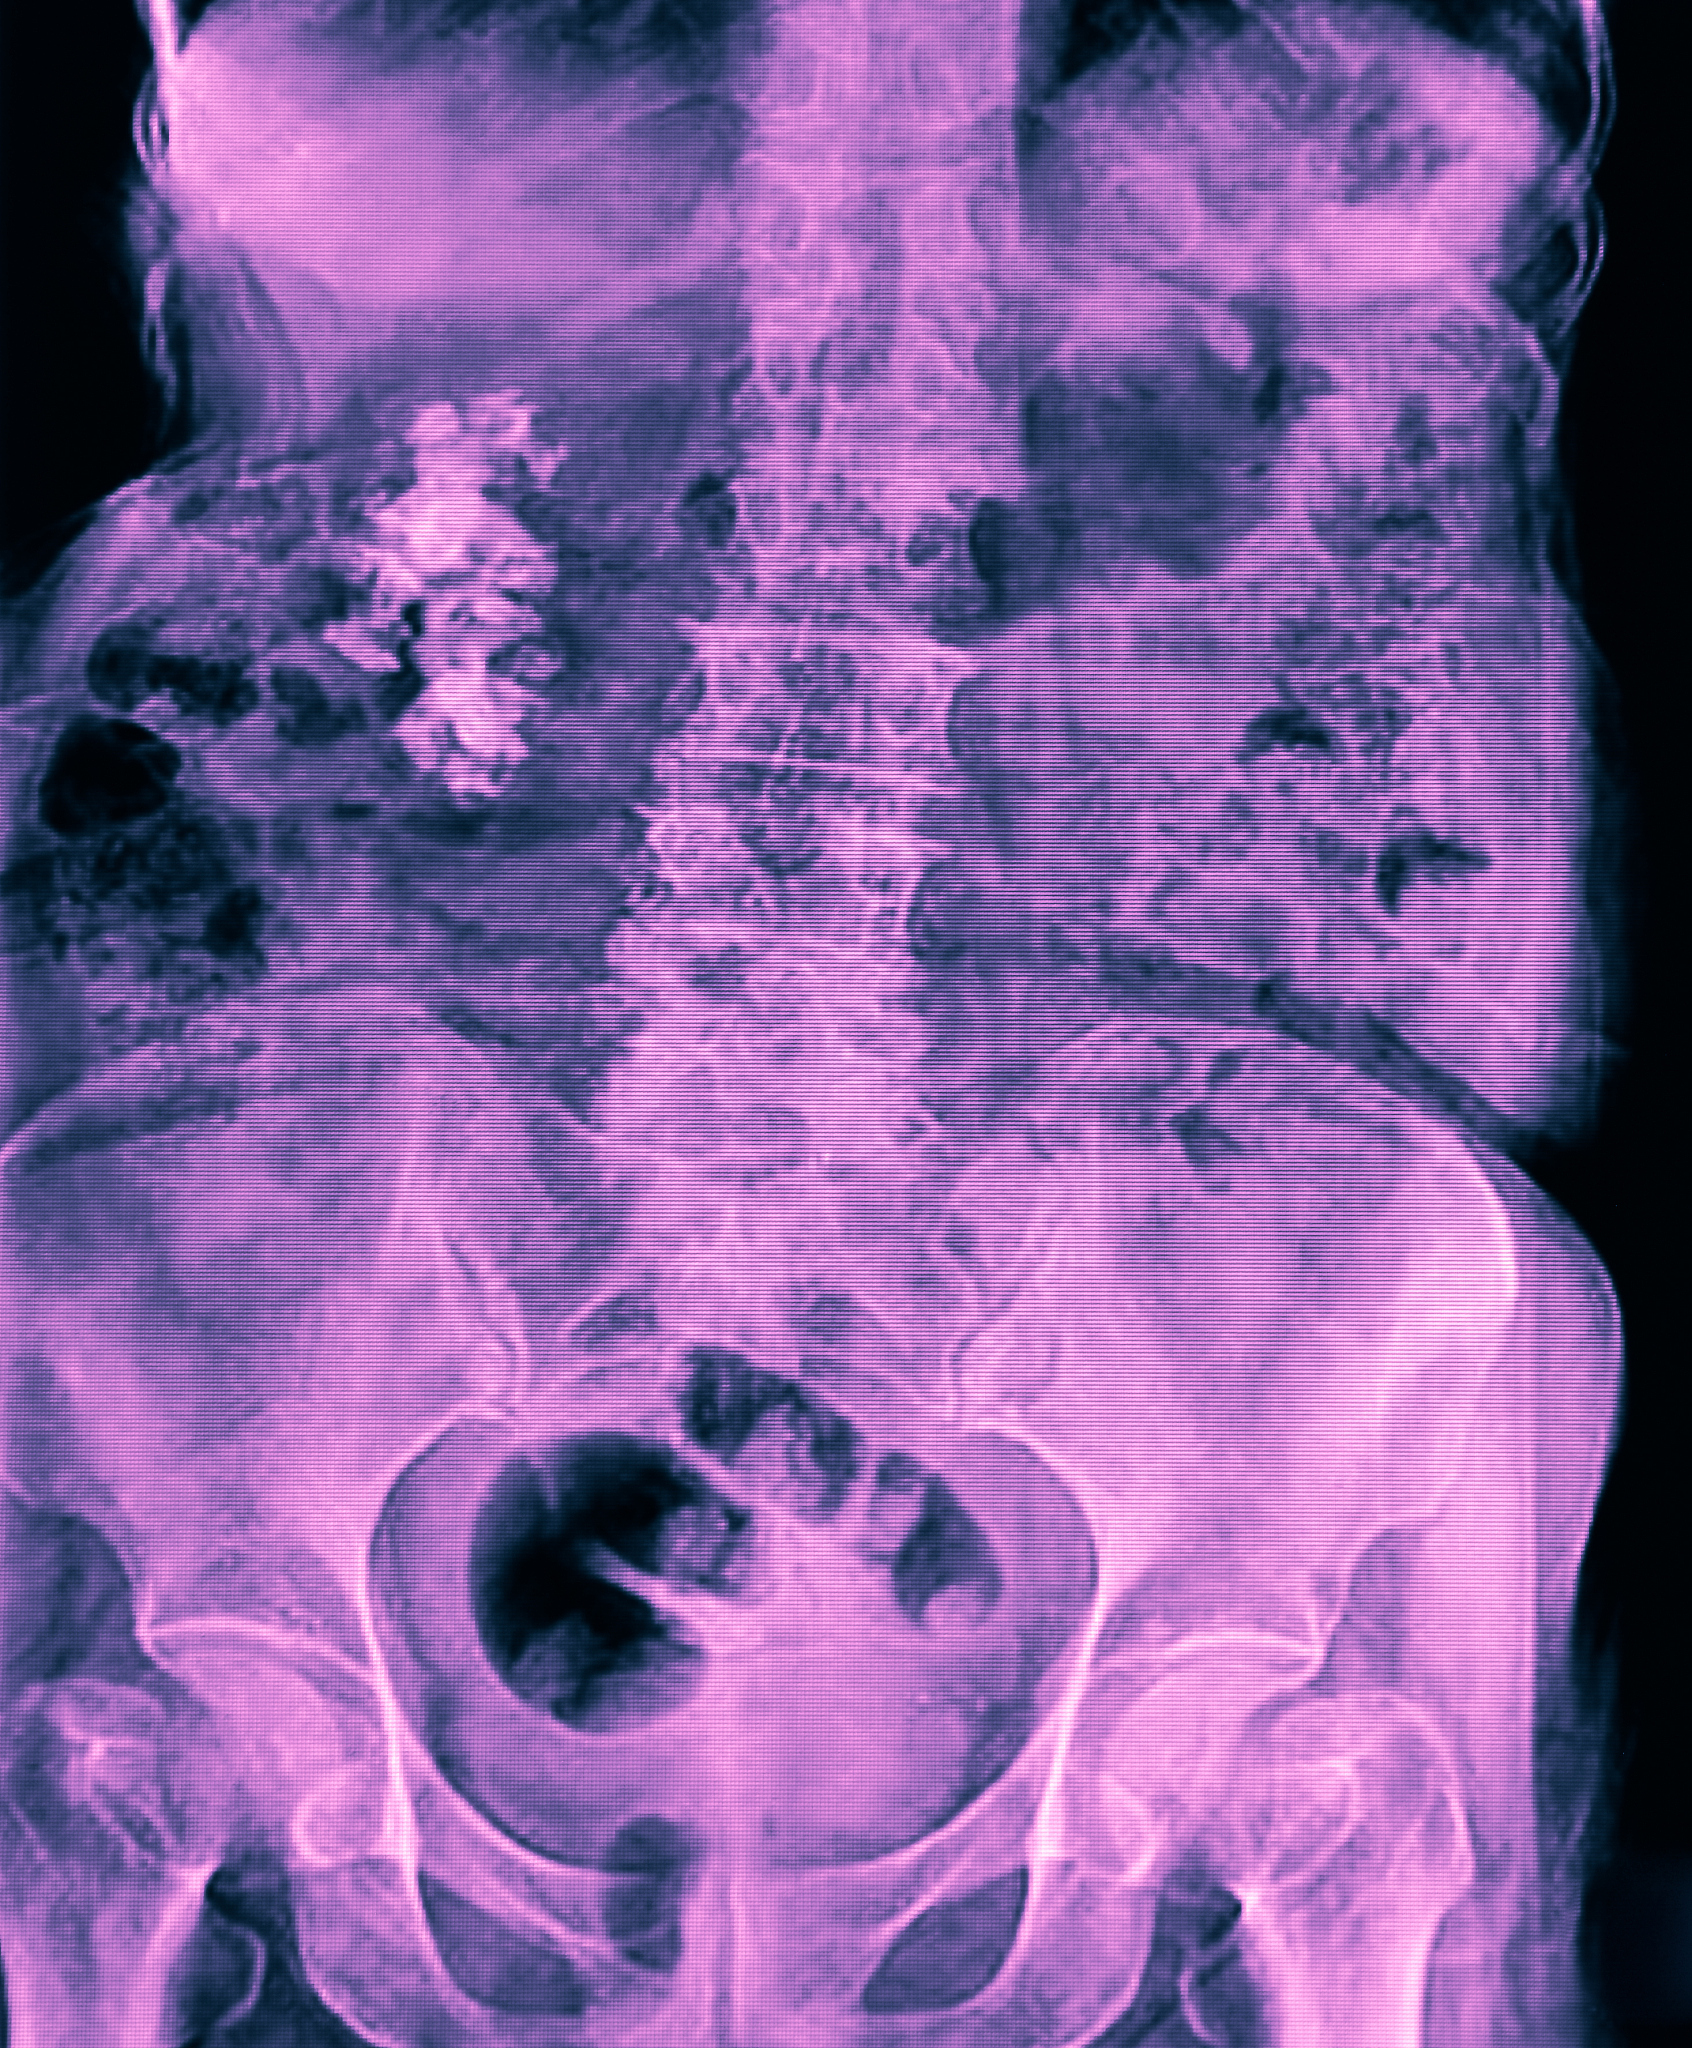

尿酸与肾结石的关系是比较密切的。尿酸是一种由核酸代谢产生的物质,正常情况下通过肾脏排出体外。但是,当体内尿酸过多或肾脏功能异常时,尿酸就会在肾脏中沉积形成尿酸结晶,进而形成尿酸结石。尿酸结石是肾结石中的一种,占据了大约10%的比例。而且,尿酸结石的形成与高尿酸血症有关,高尿酸血症是指体内尿酸含量过高,是尿酸结石形成的主要原因之一。因此,降低血尿酸水平可以有效预防和治疗尿酸结石。